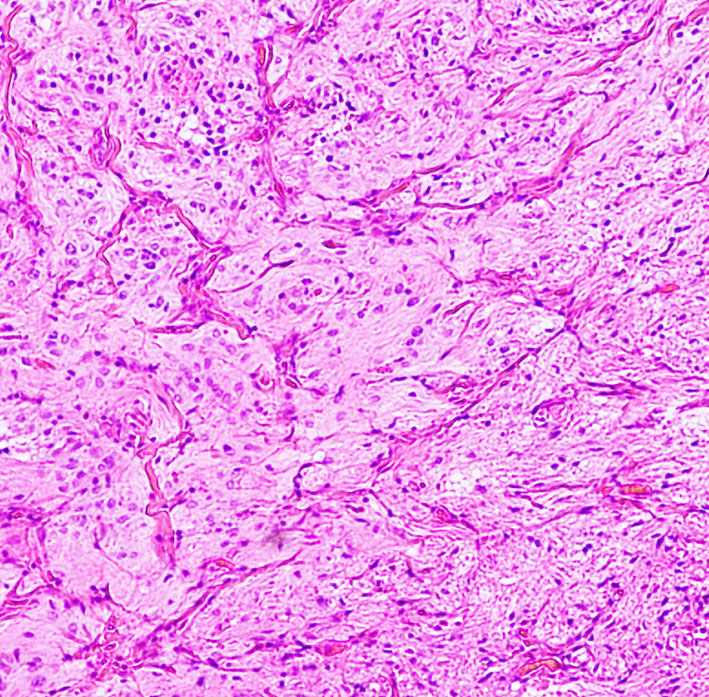

病理です。10歳くらいになるので疎な部分と密な部分が混在します。左側は,幼児型のpilocytic astrocytomaの非常に疎な組織で,吸引管で簡単に吸い取ることができる部分です。右側は,グリア組織が発達してコンパクトな部分で切り取らなければ切除できません。このような部分を小脳表面からむしり取ると,小脳白質損傷を招きます。ガドリニウム増強される部分の腫瘍は柔らかいという特徴があります。